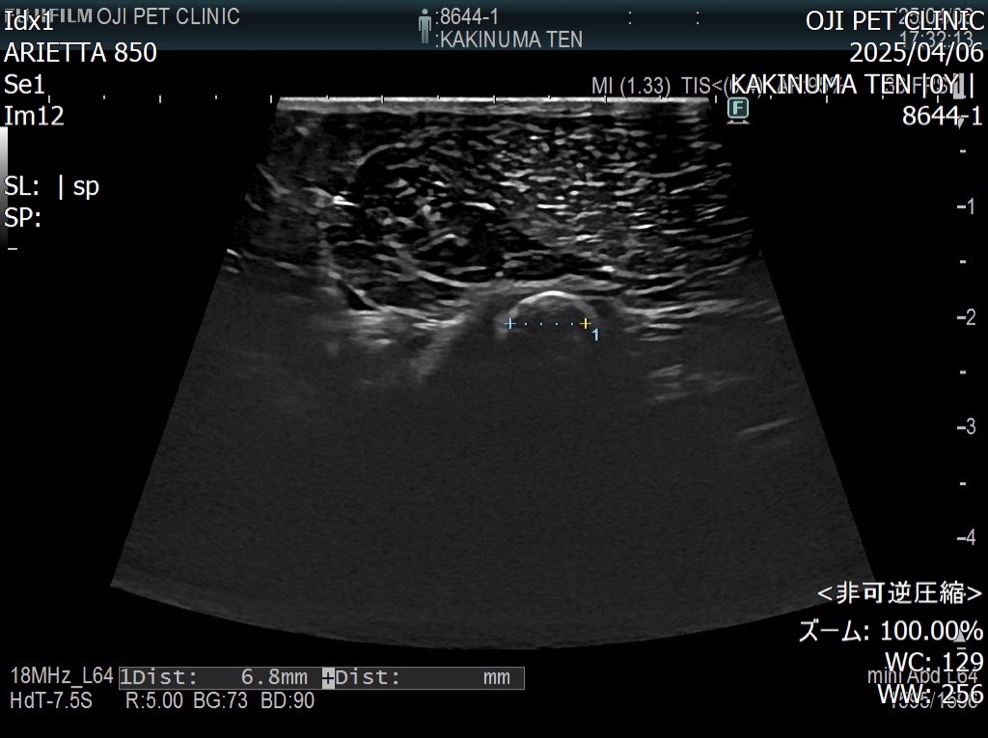

超音波検査にて膀胱内には結石が認められないことを確認